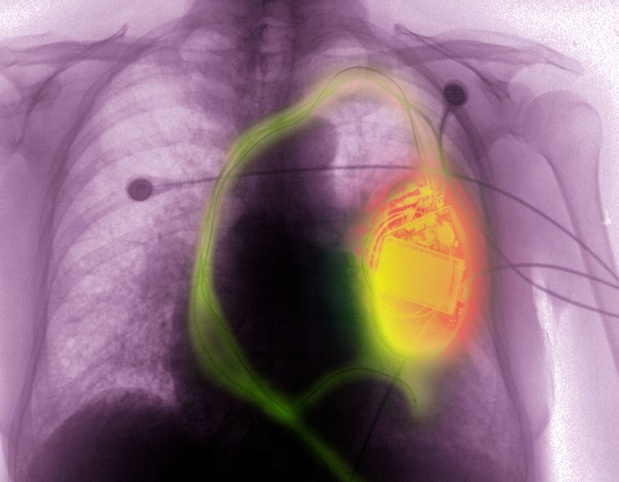

Cardiologen van UZ Leuven hebben bij een Belgische patiƫnt voor het eerst een nieuw type minipacemaker geplaatst, dat voor meer dan 80 procent van de patiƫnten geschikt is. De nieuwe pacemaker, die draadloos is, kan de twee kamers van het hart stimuleren, wat een belangrijke doorbraak is.